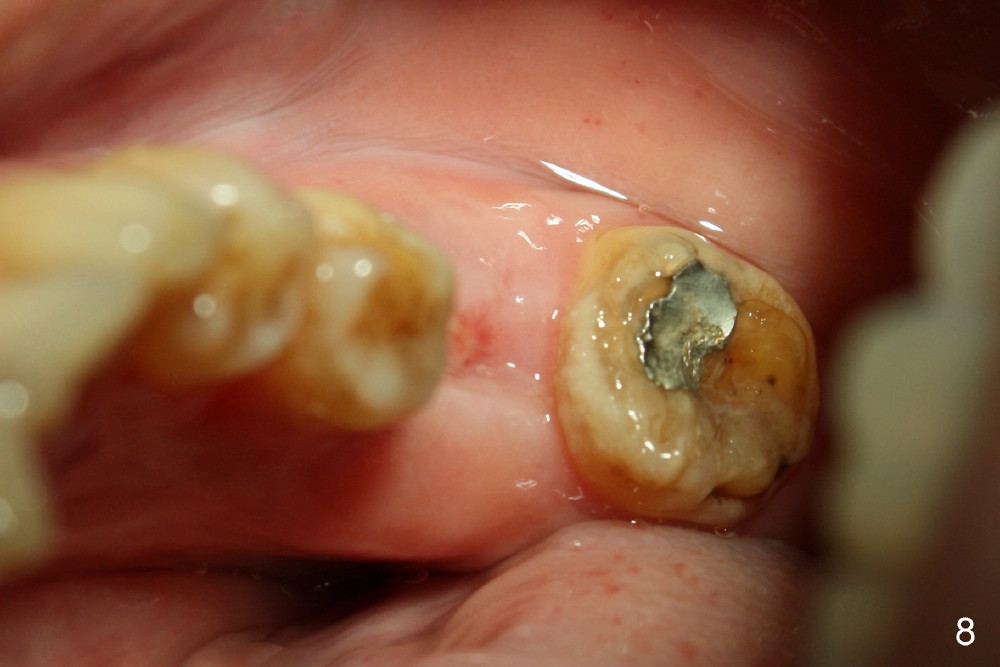

The tooth #30 was extracted in other office 1 month ago. The socket appears to heal normally. A tissue-level implant is placed as planned and smoothly. No antibiotic is prescribed pre- or post-op. The patient reports mild pain 1 week postop. There is a sign of infection. Amoxicillin is prescribed. One week later, the symptom improves, but the infection signs are present (Fig.1). The implant has mobility and is removed (Fig.2). The osteotomy is thoroughly debrided, followed by copious irrigation with normal saline and Clindamycin soaking. Irradiated cancellous bone graft (.5 mg) is placed (Fig.3,4). The wound is covered by collagen plug (Fig.5) and sutured with Chromic gut (Fig.6). Amoxicilin is prescribed postop. One week follow up reveals normal wound healing (Fig.7 (buccal view), 8 (lingual)).